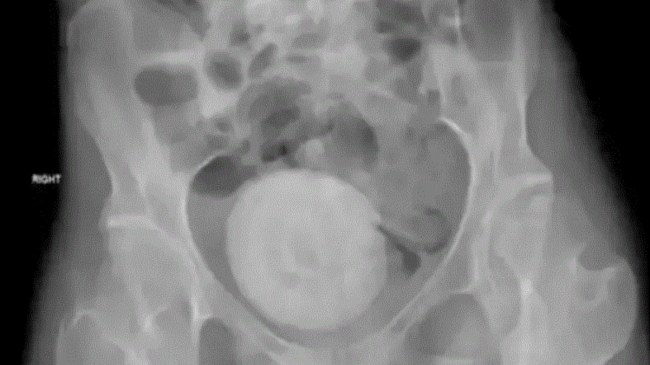

मेडिकल साइंस में कभी-कभी ऐसे दुर्लभ मामले सामने आते हैं जिनपर डॉक्टर भी हैरान रह जाते हैं। ऐसा ही एक मामला लेबनान की महिला में पाया गया है, जो काफी चौंकाने वाला है। लेबनान में एक महिला के पेल्विस में संतरे के आकार का ‘वजाइना स्टोन’ पाया गया है। इसकी तस्वीरें भी सामने आईं हैं। इसका पता तब चला जब महिला को पेट में तेज दर्द होने लगी और उसे अस्पताल ले जाया गया। उसे लगातार दर्द रहता था। इसके साथ ही उल्टी और बेचैनी भी रहती थी।

इसके बाद महिला को लेबनीज़ विश्वविद्यालय ले जाया गया। डॉक्टरों ने लेजर की मदद से इस पथरी को हटा दिया है। इस सर्जरी में तीन घंटे का समय लगा। सामने आई एक्स रे की तस्वीरों में महिला के ज्यादातर पेल्विक एरिया में पथरी दिखाई दे रही है। महिला की उम्र 27 साल है। डॉक्टरों को जैसे ही पेल्विस में पथरी का पता चला महिला की ठीक तरीके से जांच की गई।

टाइम्स नाउ की एक रिपोर्ट के मुताबिक मेडिकल जर्नल न्यूरोलॉजी केस रिपोर्ट्स में छपे मामले में कहा गया है कि यह पथरी तब विकसित होती है जब योनि में रुका हुआ मूत्र जमा हो जाता है। यह कठोर क्रिस्टल बनाता है और लगातार बढ़ता रहता है। हालांकि गुर्दे में पथरी तो आम बात है और इसके बहुत से मामले सामने आते हैं, लेकिन योनि में पथरी अत्यंत दुर्लभ है। मेडिकल साइंस के इतिहास में अभी तक इसके 100 से भी कम केस सामने आए हैं।